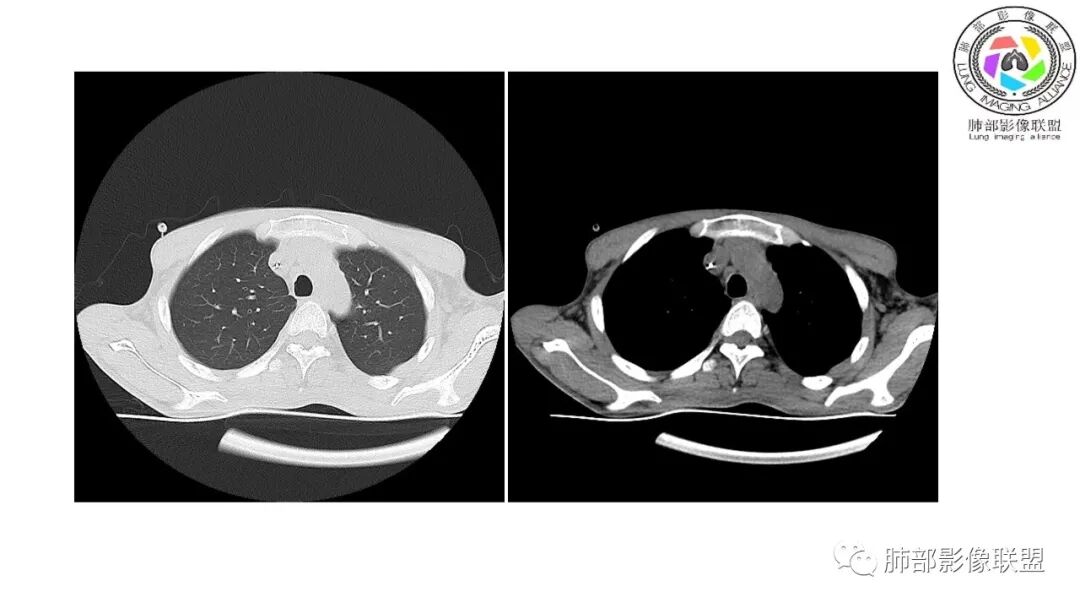

影像与临床:1.青年男性,HlV阳性,颜面部皮疹(未提供皮疹图像)、发热(高热),实验室CRP、PCT高,T-Spot阴性。2.右肺下叶空洞结节,壁厚不均,边界清楚,其内线状影,未见液平及钙化,未见卫星灶,纵隔淋巴结增大,双侧腋窝见增大淋巴结。心腔内低密度提示贫血可能。肝脾影增大,未见结节影及块影。腹膜后见多发增大淋巴结。

综合分析:本例肺部影像学改变并不具有特征性,空洞性病灶须与多种疾病鉴别,但年轻HIV阳性患者,高热,皮疹,肝脾增大,纵隔、腋窝、腹膜后见多发增大淋巴结等都强烈提示马尔尼菲篮状菌感染的可能性。